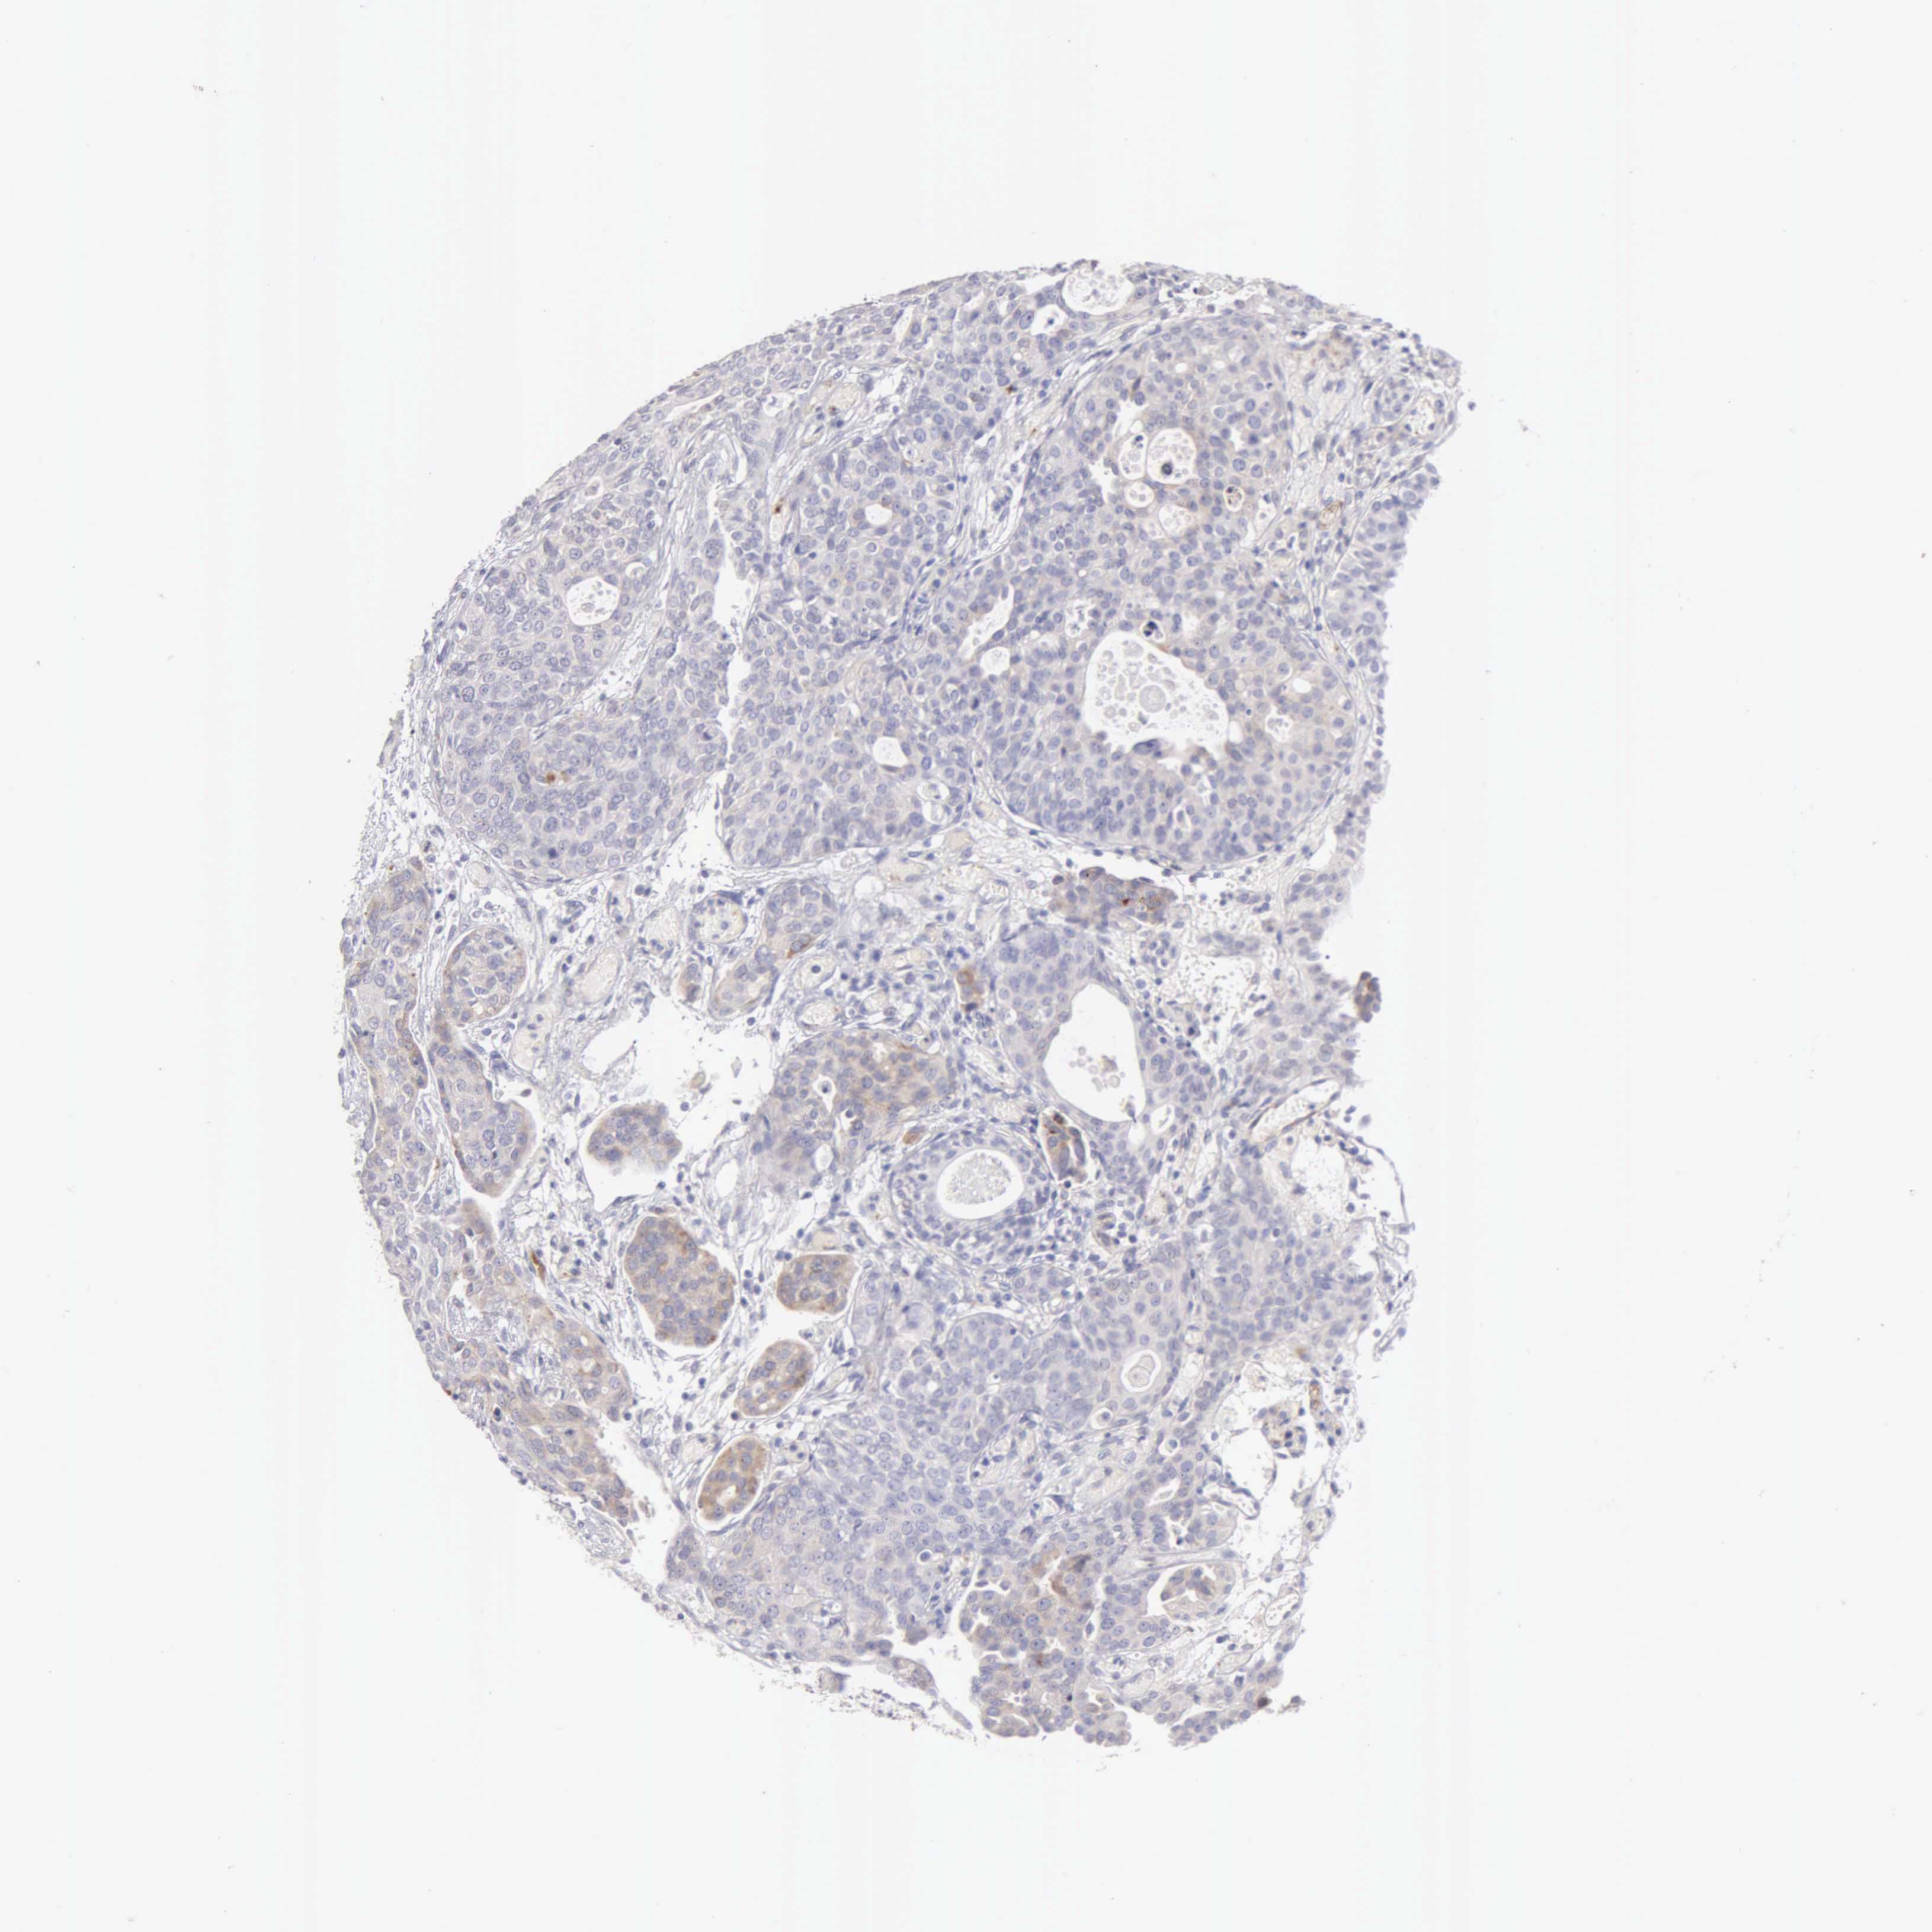

UROTHELIAL CANCER - Protein expressioni

A mouse-over function shows sample information and annotation data. Click on an image to view it in a full screen mode. Samples can be filtered based on level of antibody staining by selecting one or several of the following categories: high, medium, low and not detected. The assay and annotation is described here.

Note that samples used for immunohistochemistry by the Human Protein Atlas do not correspond to samples in the TCGA dataset.

Antibody stainingi

Antibody staining in the annotated cell types in the current human tissue is reported as not detected, low, medium, or high, based on conventional immunohistochemistry profiling in selected tissues. This score is based on the combination of the staining intensity and fraction of stained cells.

Each image is clickable and will lead to virtual microscopy that enables deeper exploration of all samples and also displays staining intensity scores, fraction scores and subcellular localization as well as patient and tissue information for each sample.

Antibody HPA001462

Antibody CAB000157

Staining

High

Medium

Low

Not detected

Intensity

Strong

Moderate

Weak

Negative

Quantity

>75%

75%-25%

<25%

None

Location

Nuclear

Cytoplasmic/membranous

Cytoplasmic/membranous,nuclear

Urothelial carcinoma, High grade